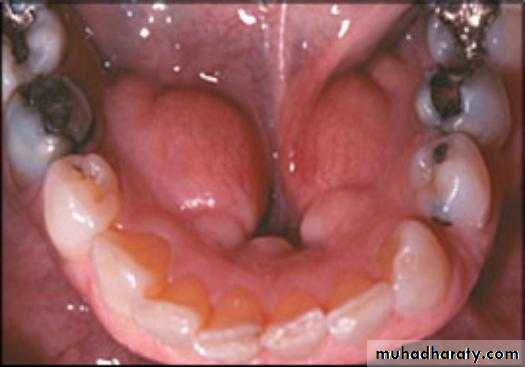

Torus mandibularis:

Usually occurs bilaterally, on the lingual surface of body of the mandible.

Tori should be removed if the patient is to wear the removable partial denture with any degree of comfort.

Exostoses and undercuts:

That are present in residual ridge areas that prevent the proper extension of the denture borders should be evaluated and , if necessary, surgically corrected.4/2/2018